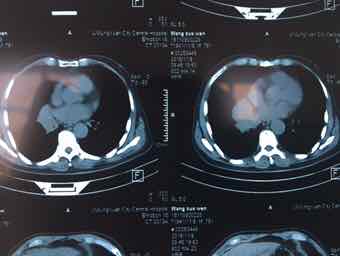

男,74岁,咳嗽咳痰3个月,无发热,无胸痛,无盗汗,无咳血。右肺占位性质待查?完善气管镜检查